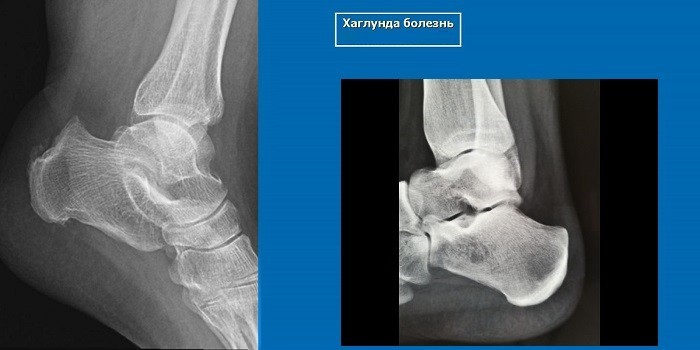

Рентгенологические признаки болезни Шинца

Самое информативное изображение – боковая проекция пятки. Признаки синдрома Шинца на рентгене:

- неоднородность ядра окостенения;

- пятна в области поражения;

- смещение в сторону секвестроподобных теней;

- отделение осколков;

- на некоторых участках кости сформировано новое вещество;

- щель между апофизом и пяточной костью;

- места костного разрыхления.